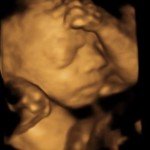

4D/5D/HD Ultrasound Gallery

Gallery